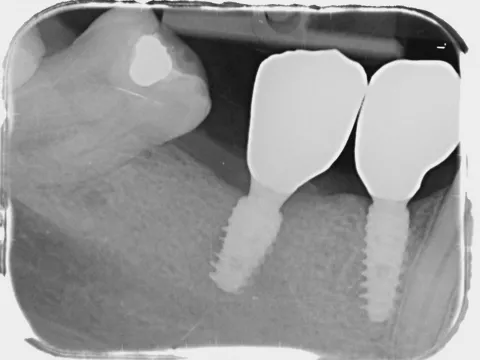

10. Periapical radiograph taken on day 3 post surgery showing the implant with the HealFit® SH healing abutment in position.

10

17a. 17b. Periapical radiograph of the implant at tooth position (LL5 LL4 and UL4 and), obtained 4 months post‑implantation

17a

17b